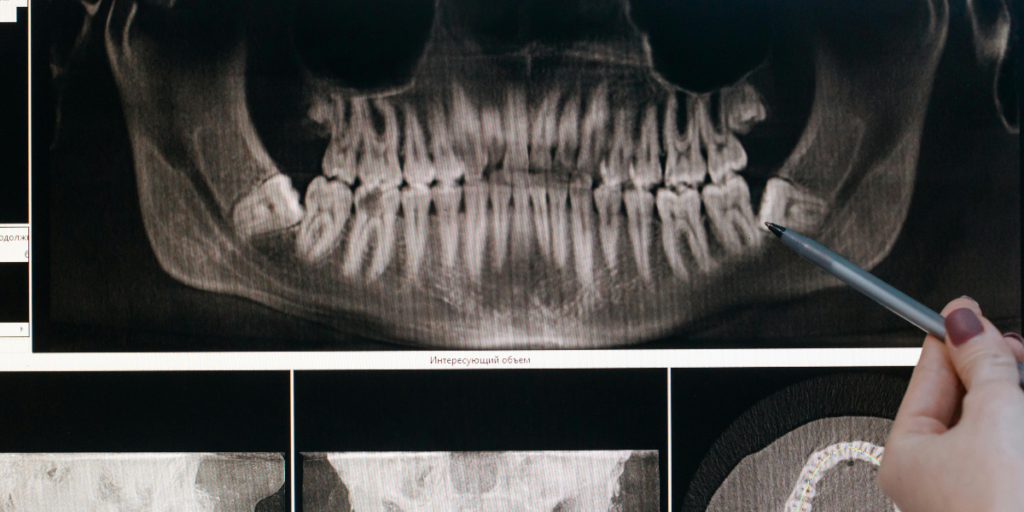

Digital X-Rays And 3D Imaging

X-rays can show signs of infection or bone changes near the root. 3D imaging can help with complex cases and root concerns. Imaging helps decide if a crown can work or if the crack is too deep. It also helps guide a safe plan.